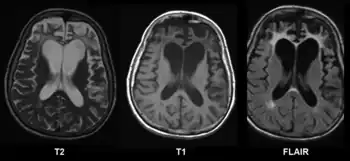

A range of neuropsychological tests are available for clarifying the nature and extent of frontal lobe dysfunction. For example, concept formation and ability to shift mental sets can be measured with the Wisconsin Card Sorting Test, planning can be assessed with the Mazes subtest of the WISC.[3] Frontotemporal dementia shows up as atrophy of the frontal cortex on MRI.[20] Frontal impairment due to head injuries, tumours or cerebrovascular disease will also appear on brain imaging.[4]